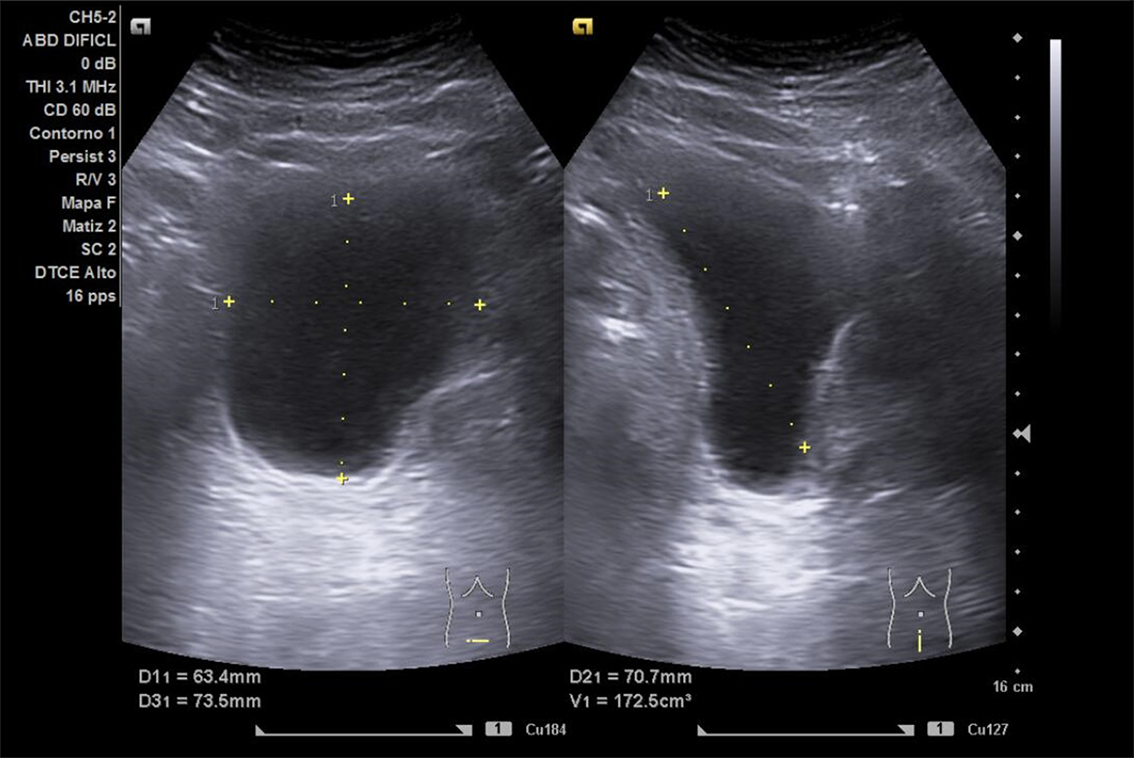

Descripción de los hallazgos ecográficos y las imágenes más relevantes para la resolución del caso

Se realiza ECO POCUS en la que se aprecia riñón derecho de morfología y tamaño normal. Riñón izquierdo con hidronefrosis grado III. A nivel de vejiga, bien replecionada se aprecia masa a nivel de pared izquierda adyacente a unión ureterovesical de 1.8 x 2,7 cm Ausencia de jet izquierdo.